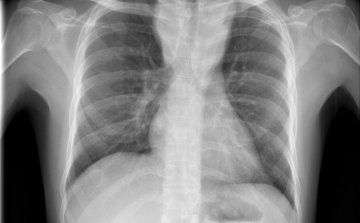

Terjed a tbc Szatymazon?

Hétfő reggel óta tbc-tesztet végeznek el a gyerekeken egy szatymazi általános iskolában, ahol egy hete fertőző tüdőbetegségben halt meg egy korábban ott dolgozó nő - közölték az M1 aktuális csatorna déli Híradójában.